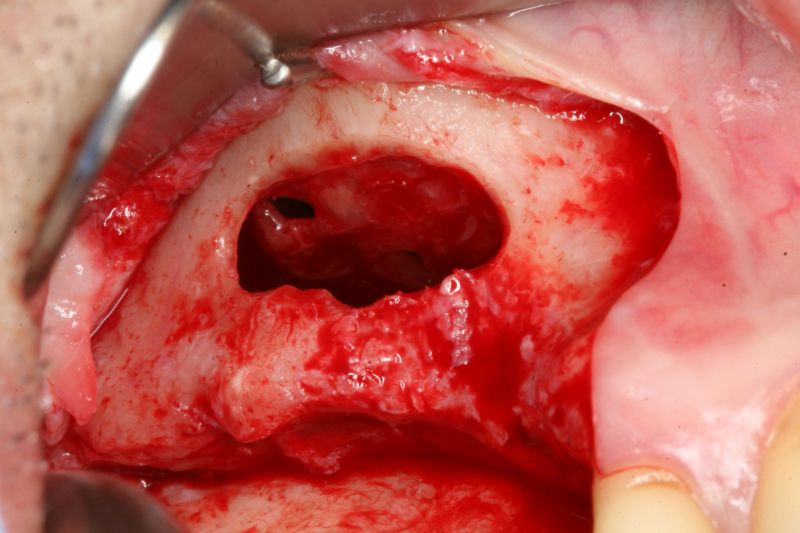

Ridge splitting with maxresorb® and collprotect® membrane - Dr. J. Neugebauer

Surgical presentation of the alveolar ridge with reduced amount of horizontal bone available